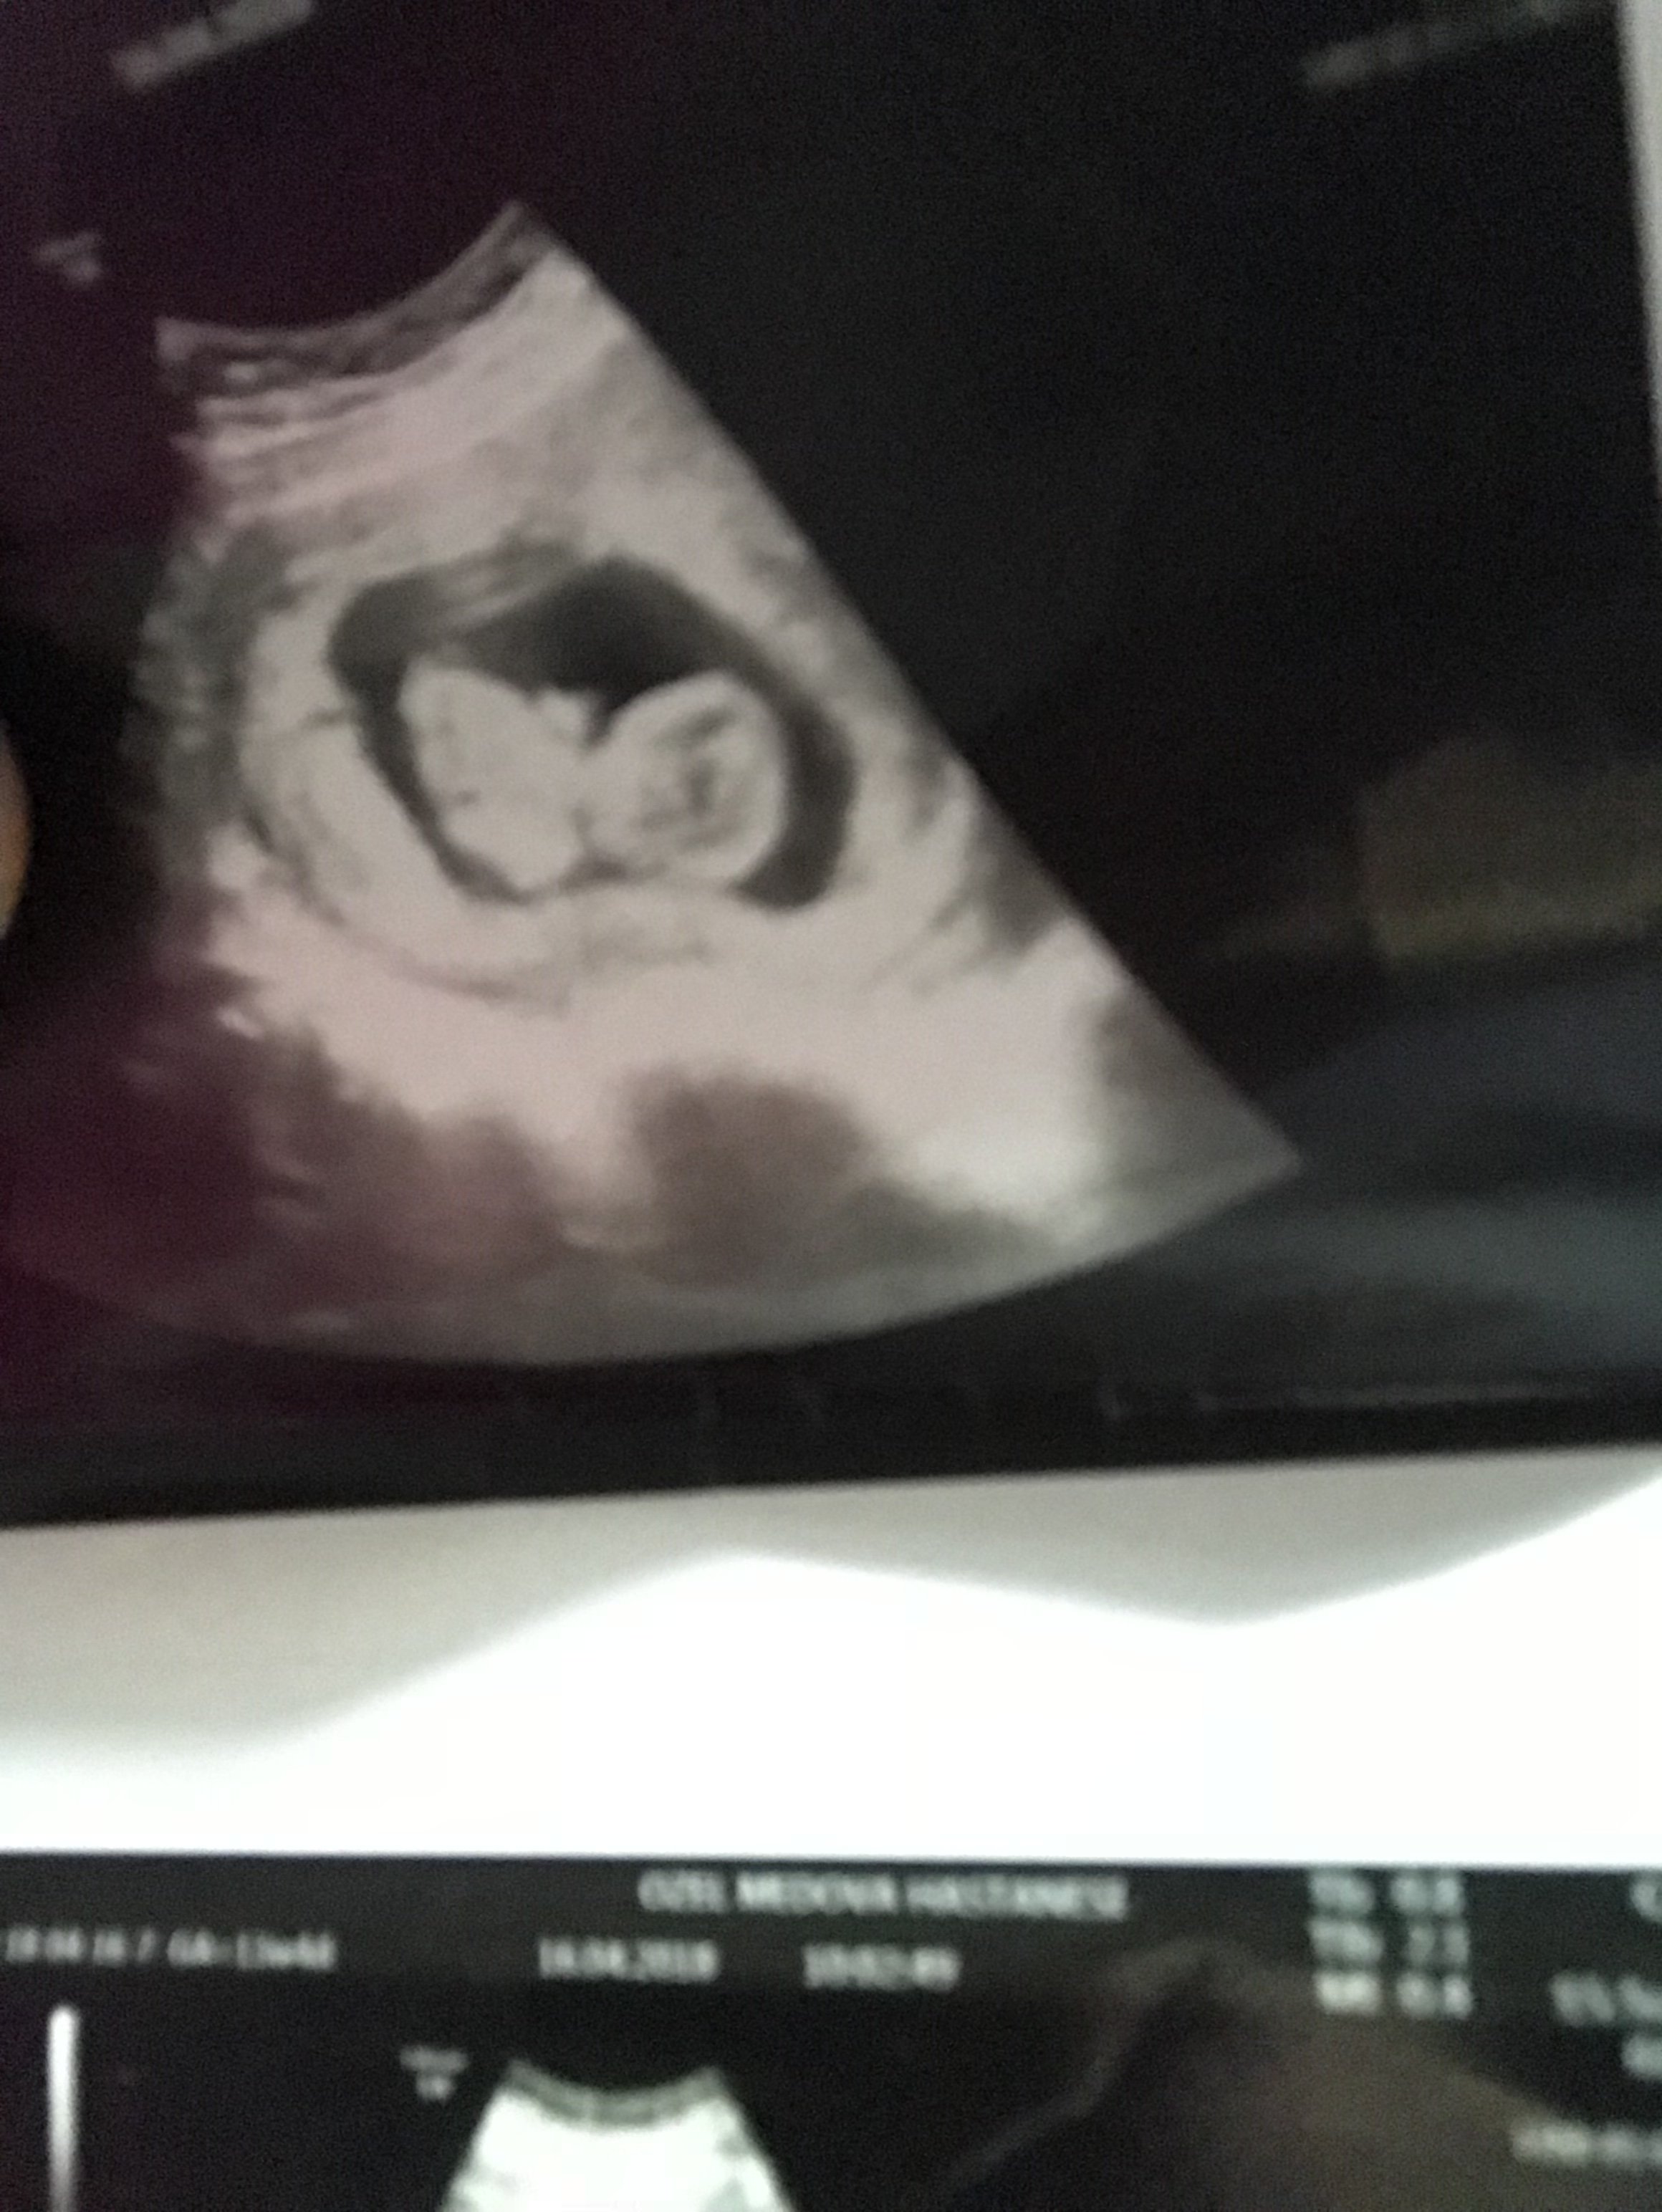

Daha önce de belirtildiği gibi, hem erkek hem de kız fetusların gelişme aşamalarında genital bir tüberkül vardır. Bu genital tüberkül bir nub olarak adlandırılır.Nub Teorisini kullanarak bebeğinizin cinsiyetini belirlemek, büyük oranda ultrason resmine bağlıdır. Bu, nub resminin sonucu belirlemeniz için mükemmel olması gerektiği anlamına gelir.

Resimde gördüğünüz gibi üst taraftaki çıkıntı paralel ise bebek kız, 30° lik açıyla yukarı bakıyorsa bebek erkektir.

Gebeliğin 9. haftası fetusun bacaklarının arasın da küçük bir çıkıntı görülür. Gebeliğin 12. ve 14 haftası bu topak çıkıntı nın açısı değerlendirilerek , cinsiyet tahmini yapılır. Çıkıntı kızlar da 30 derecenin altın da ve düzdür erkekler de ise 30 derecelik açıdan büyüktür.

Görünürlük , omurga ile ilgili genital tüberkül açısı , Gölgeler ve erkek belirteçler ve topak çevreleyen ucu , Gebelik yaşına göre uzunluğu da dahil olmak üzere, şekil.. Nub teorisi ile cinsiyet belirleme de tarama omurga görüntüleme ve buna özü ilişkisini sağlamak için, profil görünümünde olmalıdır.